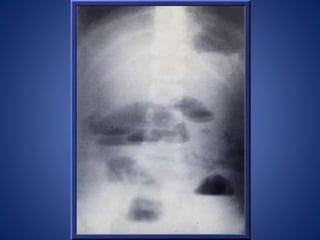

Volvulus x ray:Sigmoid volvulus - 'coffee bean' sign The sigmoid colon is very dilated because it is twisted at the root of its mesentery in the left iliac fossa (LIF) The twisted loop of sigmoid colon is said to resemble a coffee bean